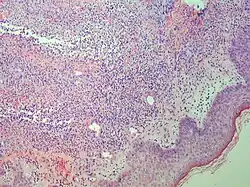

Sweet syndrome (SS), or acute febrile neutrophilic dermatosis,[1][2] is a skin disease characterized by the sudden onset of fever, an elevated white blood cell count, and tender, red, well-demarcated papules and plaques that show dense infiltrates by neutrophil granulocytes on histologic examination.

Studies show a moderate neutrophilia (less than 50%), elevated ESR (greater than 30 mm/h) (90%), and a slight increase in alkaline phosphatase (83%). Skin biopsy shows a papillary and mid-dermal mixed infiltrate of polymorphonuclear leukocytes with nuclear fragmentation and histiocytic cells. The infiltrate is predominantly perivascular with endothelial-cell swelling in some vessels, but vasculitic changes (blood clots; deposition of fibrin, complement, or immunoglobulins within the vessel walls; red blood cell extravasation;inflammatory infiltration of vascular walls) are absent in early lesions.Perivasculitis occurs secondarily, because of cytokines released by the lesional neutrophils. True transmural vasculitis is not an expected finding histopathologically in SS.

Sweet described a disease with four features: fever; leukocytosis; acute, tender, red plaques; and a papillary dermal infiltrate of neutrophils. This led to the name acute febrile neutrophilic dermatosis. Larger series of patients showed that fever and neutrophilia are not consistently present. The diagnosis is based on the two constant features, a typical eruption and the characteristic histologic features; thus the eponym "Sweet's syndrome" is used.